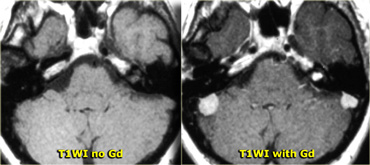

Conspicuity of tumors with contrast

The case on the left demonstrates the value of Gadolinium in the conspicuity of tumors.

This is a patient with Neurofibromatosis II.

After the administration of contrast the two meningiomas and the schwannoma are easily seen.